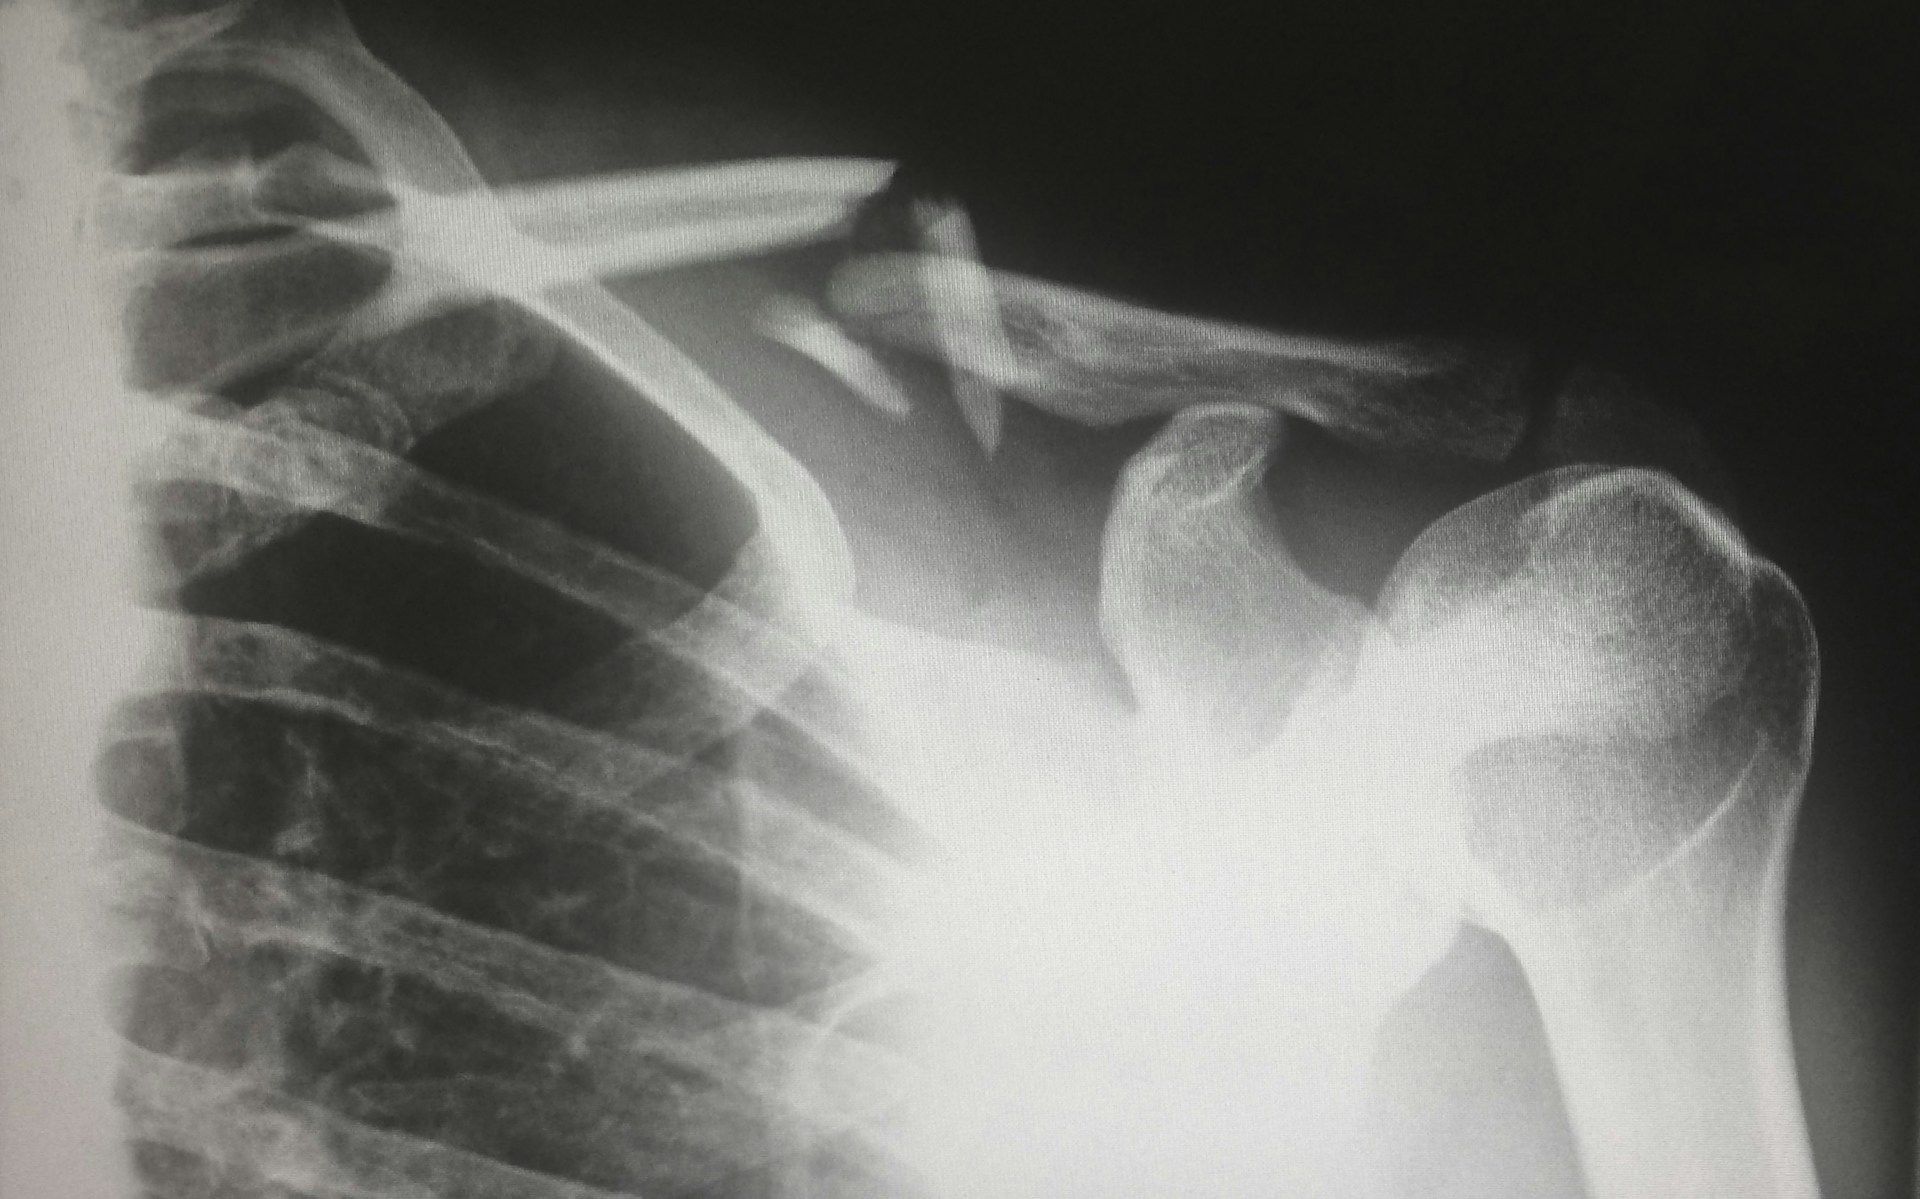

Китайські науковці взяли приклад із природи: надихнувшись тим, як устриці кріпляться до поверхонь під водою, вони створили абсолютно нову формулу клею під назвою Bone-02. Особливість цього клею – виняткова адгезія навіть у складних умовах, наприклад, при кровотечі, де інші сполуки безсилі.

Ще один важливий момент: Bone-02 поступово розсмоктується у процесі природного відновлення кістки і не потребує повторних операцій з видалення імплантів. Його міцність на зсув досягає 0,5 мегапаскаля,

Ця інновація вже пройшла випробування на 150 пацієнтах: у багатьох випадках те, що раніше вимагало металоконструкцій і складних операцій, тепер вирішується за три хвилини за допомогою нового клею.

Клей Bone-02 особливо перспективний для екстреної медицини й лікування тяжких уламкових переломів, коли на рахунку кожна хвилина, а надійність фіксації критично важлива.